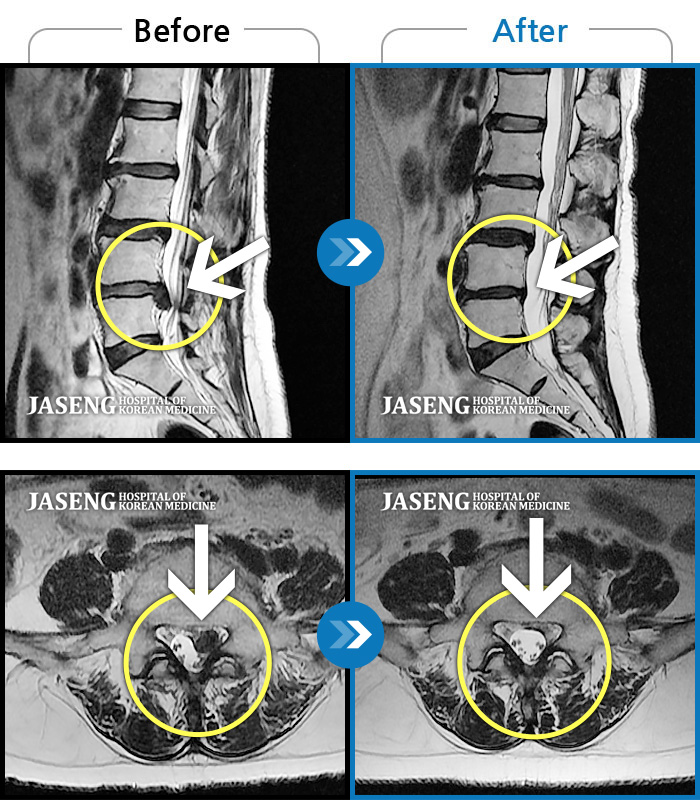

Before

After

환자에게 사전 동의를 받아 동일 조건에서 촬영되었습니다.

개인에 따라 치료 후 부작용이 발생할 수 있으니 의료진과 상담 후 치료를 진행하시기 바랍니다.

좌측 하요추부 통증과 좌측 하지 전면 비증

좌측 허리부터 좌측 대퇴 후면까지 당기는 통증